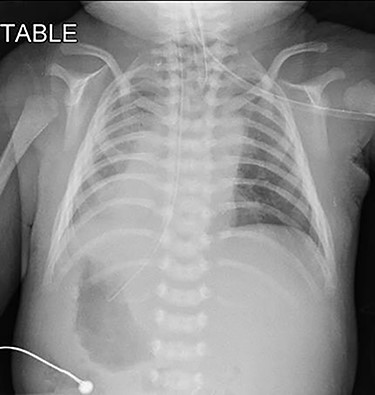

Upon arrival at our center, he was severely cyanosed, with oxygen saturations of 50–60% on maximum dose of propranolol and prostaglandin infusion. On physical examination, there was an ejection systolic murmur of a grade 3/6. As previously noted the chest radiograph (Fig. 1) revealed apparent dextrocardia with visceral situs inversus. The echocardiography showed tetralogy anatomy, dextrocardia, left aortic arch and severe infundibular stenosis with pressure gradient of 85 mmHg. The PDA appeared constricted, but its origin was not visualized. The pulmonary valve annulus was 4.7 mm (−4 SD) and main pulmonary artery (MPA) was 5.8 mm whilst the size of the branches were within the acceptable limit (−1.0 SD).

Pre-operative chest radiograph showed apparent dextrocardia and visceral situs inversus (evidenced by lower tip of feeding tube in the right-sided stomach with left-sided homogenous liver opacity).